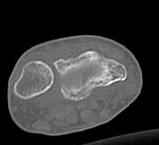

Уважаемые коллеги.Прошу обсудить случай лечения перелома дистального метаэпифиза лучевой кости. Ситуация скандальная и крайне неблагоприятная. Больная с патологической обстоятельностью мышления, склонностью к сутяжничеству, патологическими умозаключениями, не поддающимися коррекции (см. психиатрию, правда офиц. диагноза нет). В данном случае есть ряд ошибок с нашей стороны, прежде всего в отношении качества ведения документации (за что получил административное взыскание, по делом мне дураку). В остальном- придерживались в лечении подхода классический советской школы. Так как умную операцию…… сами знаете… 15.12- перелом луча в Москве. Там же репозиция, гипс. Дальнейшее лечение у нас в ЦРБ. 20.12.- вторичное смещение в гипсе21.12- под внутривенным наркозом- репозиция, гипсовая лонгета. Дальше начинается самое интересное. После репозиции больная заявила, что я (репозицию делал я) порвал ей все связки в суставе, посинел у нее 5 палец, якобы я за него тянул и т. д. На самом деле на 2 сутки после репозиции рука немного отекла и было незначительное сдавление гипсом, который был ослаблен. Дальнейшее лечение консервативное. Через 6 недель- гипс снят, назначено ЛФК. Пациентка крайне недовольна. Говорит, что на снимке у нее выступает кость, я ей сломал руку и.т.д. В общем началось. Пациентка прочитала в интернете наверное все, что есть по данной травме.По заключениями рентгенологов и консультанта из КДЦ областной больницы - стояние отломков допустимое. Объективно говоря- снижена высота лучевой кости, диастаз лучелоктевого сочленения, и не сросся шиловидный отросток. однако на РКТ при сравнении с другой стороной- разница незначительная. Дальше в одной из больниц нашей области и одной из больниц Москвы (вроде бы КГБ 53) врачи сказали, что репозиция сделана плохо. Нужна операция (восстановить длину лучевой кости), даже один из них предложил РЕДРЕССАЦИЮ (хи-хи) с наложением аппарата Илизарова. Что это для данной больной- радость неописанная. (см. описание психического статуса). Ничем другим, кроме зарабатывания дешевого авторитета объяснить данный факт не могу.Кстати, у больной еще нейропатия локтевого нерва.Для разрешения конфликта больная направлена на консультацию в ЦИТО на 03.03.11.

2. По сравнению и без ! втор смещение незначительное.НЕТ НИКАКОЙ ,,локтевой косорукости,,маделунгов . но имеется смещение совести у врачей КГБ 35--НЕТ ЗДОРОВЫХ, есть только недообследованные ! Этому смещению аппарат внешней фиксации не поможет .Психопаткам в менопаузе да весной только этого и надо чуть толкнули и поехало .